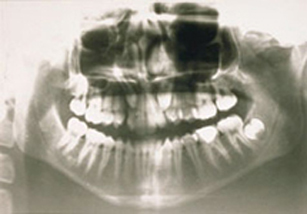

Class II Div I |